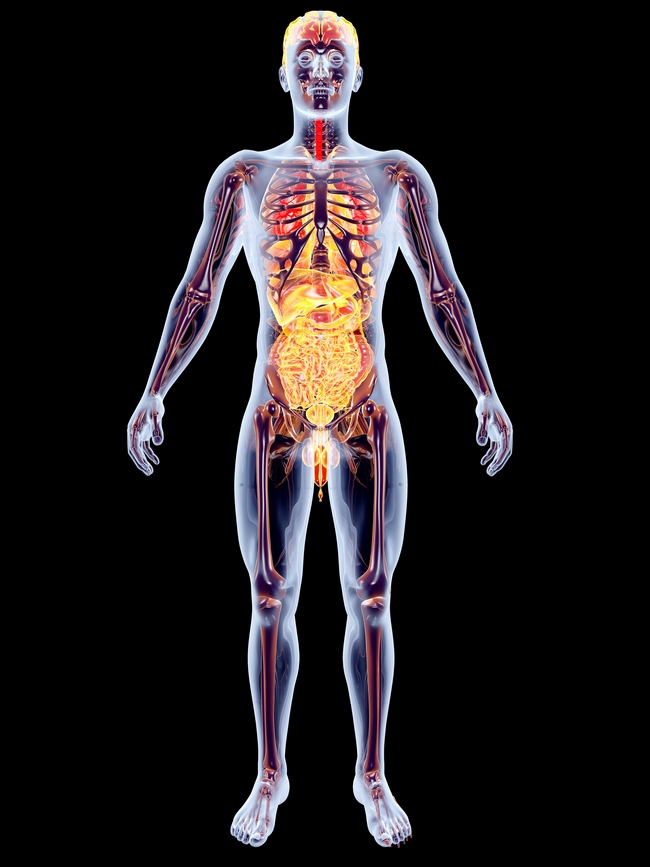

Mozek

Zdravý lidský mozek tvoří přes bilion nervových buněk a počet nervových spojů je ještě tisíckrát větší s celkovou délkou kolem 5 000 000 kilometrů. Některé mozkové buňky dokážou za vteřinu navázat spojení s 10 000 dalšími.

Největší částí mozku jsou dvě hemisféry, je to místo těch nejdokonalejších funkcí, jako je paměť, myšlení, chování, osobnost. Takzvaná paměť blaženosti vzniká v „sekci“ odměňování mozkového centra.

Jakmile se zahnízdí, je z medicínského hlediska prakticky nevymazatelná. Mozek si pak pamatuje ten blažený pocit po tučném jídle, cukru, alkoholu, cigaretě.

Zdravý mozek je hezký a čistý, v průřezu není ani celistvý, má dutá místa (mozkové komory) a ta jsou vyplněna čistou a průhlednou vodou – mozkomíšním mokem. Ten je neustále vstřebáván a kompletně se vymění za 6 hodin.

Nervový systém

Aby ten bilion nervových buněk v mozku měl co zpracovávat, posílá hřbetní mícha hlavním kanálem mezi mozkem a tělem miliony nervových impulzů za vteřinu rychlostí 434 km/h – to je jako maximální rychlost oficiálně nejrychlejšího sériově vyráběného auta Bugatti Veyron Super Sport.

Naše mícha je dlouhá 43 cm a její růst končí v pěti letech.

Srdce

Podle lékařských statistik strach nebo leknutí skutečně zodpovídá za asi 1 % infarktů u mužů a 7 % u žen. Oběhový systém u dospělého člověka je tvořený srdcem a cévami s celkovou délkou až 161 000 km.

Je to jako silniční infrastruktura, žádná buňka v těle neleží dál než pár milimetrů od jedné z krevních cév. A než krev procestuje celým systémem, to trvá pouhých 90 vteřin!

Plíce

Plíce jsou jediným orgánem, který plave na vodě, a každým nádechem se naplní vzduchem 300 milionů alveolů (plicních sklípků). Jejich celková plocha by pokryla jedno fotbalové hřiště.

Kostra

Tak jako základy domu tvoří kostra vnitřní strukturu těla. Kosti jsou 4-5krát silnější než měkká ocel, i přesto tvoří jenom 14 % celkové váhy. Možná víte, že nejsilnější kostí v lidském těle je ta stehenní.

A přestože je dutá, i tak je pevnější než železobeton, tedy pevnější než váš byt/dům. Kostní dřeň uvnitř dlouhých a plochých kostí vytváří u dospělého člověka za jednu jedinou vteřinu až 2,5 milionu nových červených krvinek.

Ty umožňují transport kyslíku z plic do každé buňky. Největším a nejsložitějším kloubem je kolenní, kyčelní pak jeden z nejsilnějších a nejstabilnějších. Drží ho pět vazů a je schopen každý den vydržet sílu až 180 kg.

Svaly

Tělo má více než 600 kosterních svalů, tvoří téměř polovinu hmotnosti člověka. Aby byly svaly ke kosti upnuté, o to se starají šlachy, které jsou často až 500krát silnější než samotné svaly a ochraňují je tak před poškozením a trhlinami.

Pokud by všechny naše svaly táhly společně a jedním směrem, vyvinuly by sílu na zvednutí břemene o váze 10 tun.